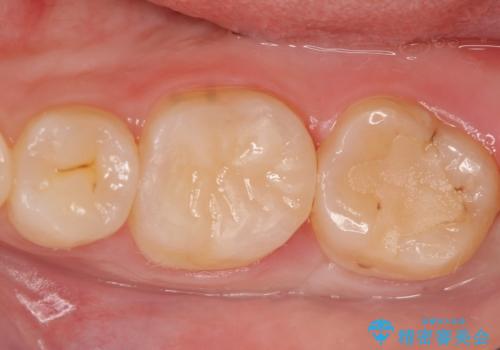

右下6は神経が死んでいたため根管治療を行い、オールセラミッククラウンによる補綴を行いました。

右下7は冷たいものがしみていたため、銀歯を除去後、オールセラミッククラウンによる補綴を行いました。

今回用いたオールセラミッククラウンはジルコニアフレームという白い素材の上にセラミックを盛っているため、審美性が非常に高いのが特徴です。

また、ジルコニアは人工ダイヤモンドの材料にも使われているほど高い強度を持っており、そのためオールセラミッククラウンは審美性だけでなく、奥歯やブリッジの補綴も可能とするクラウンです。